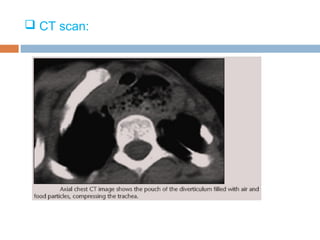

 CT scan:

3. Compression of trachea